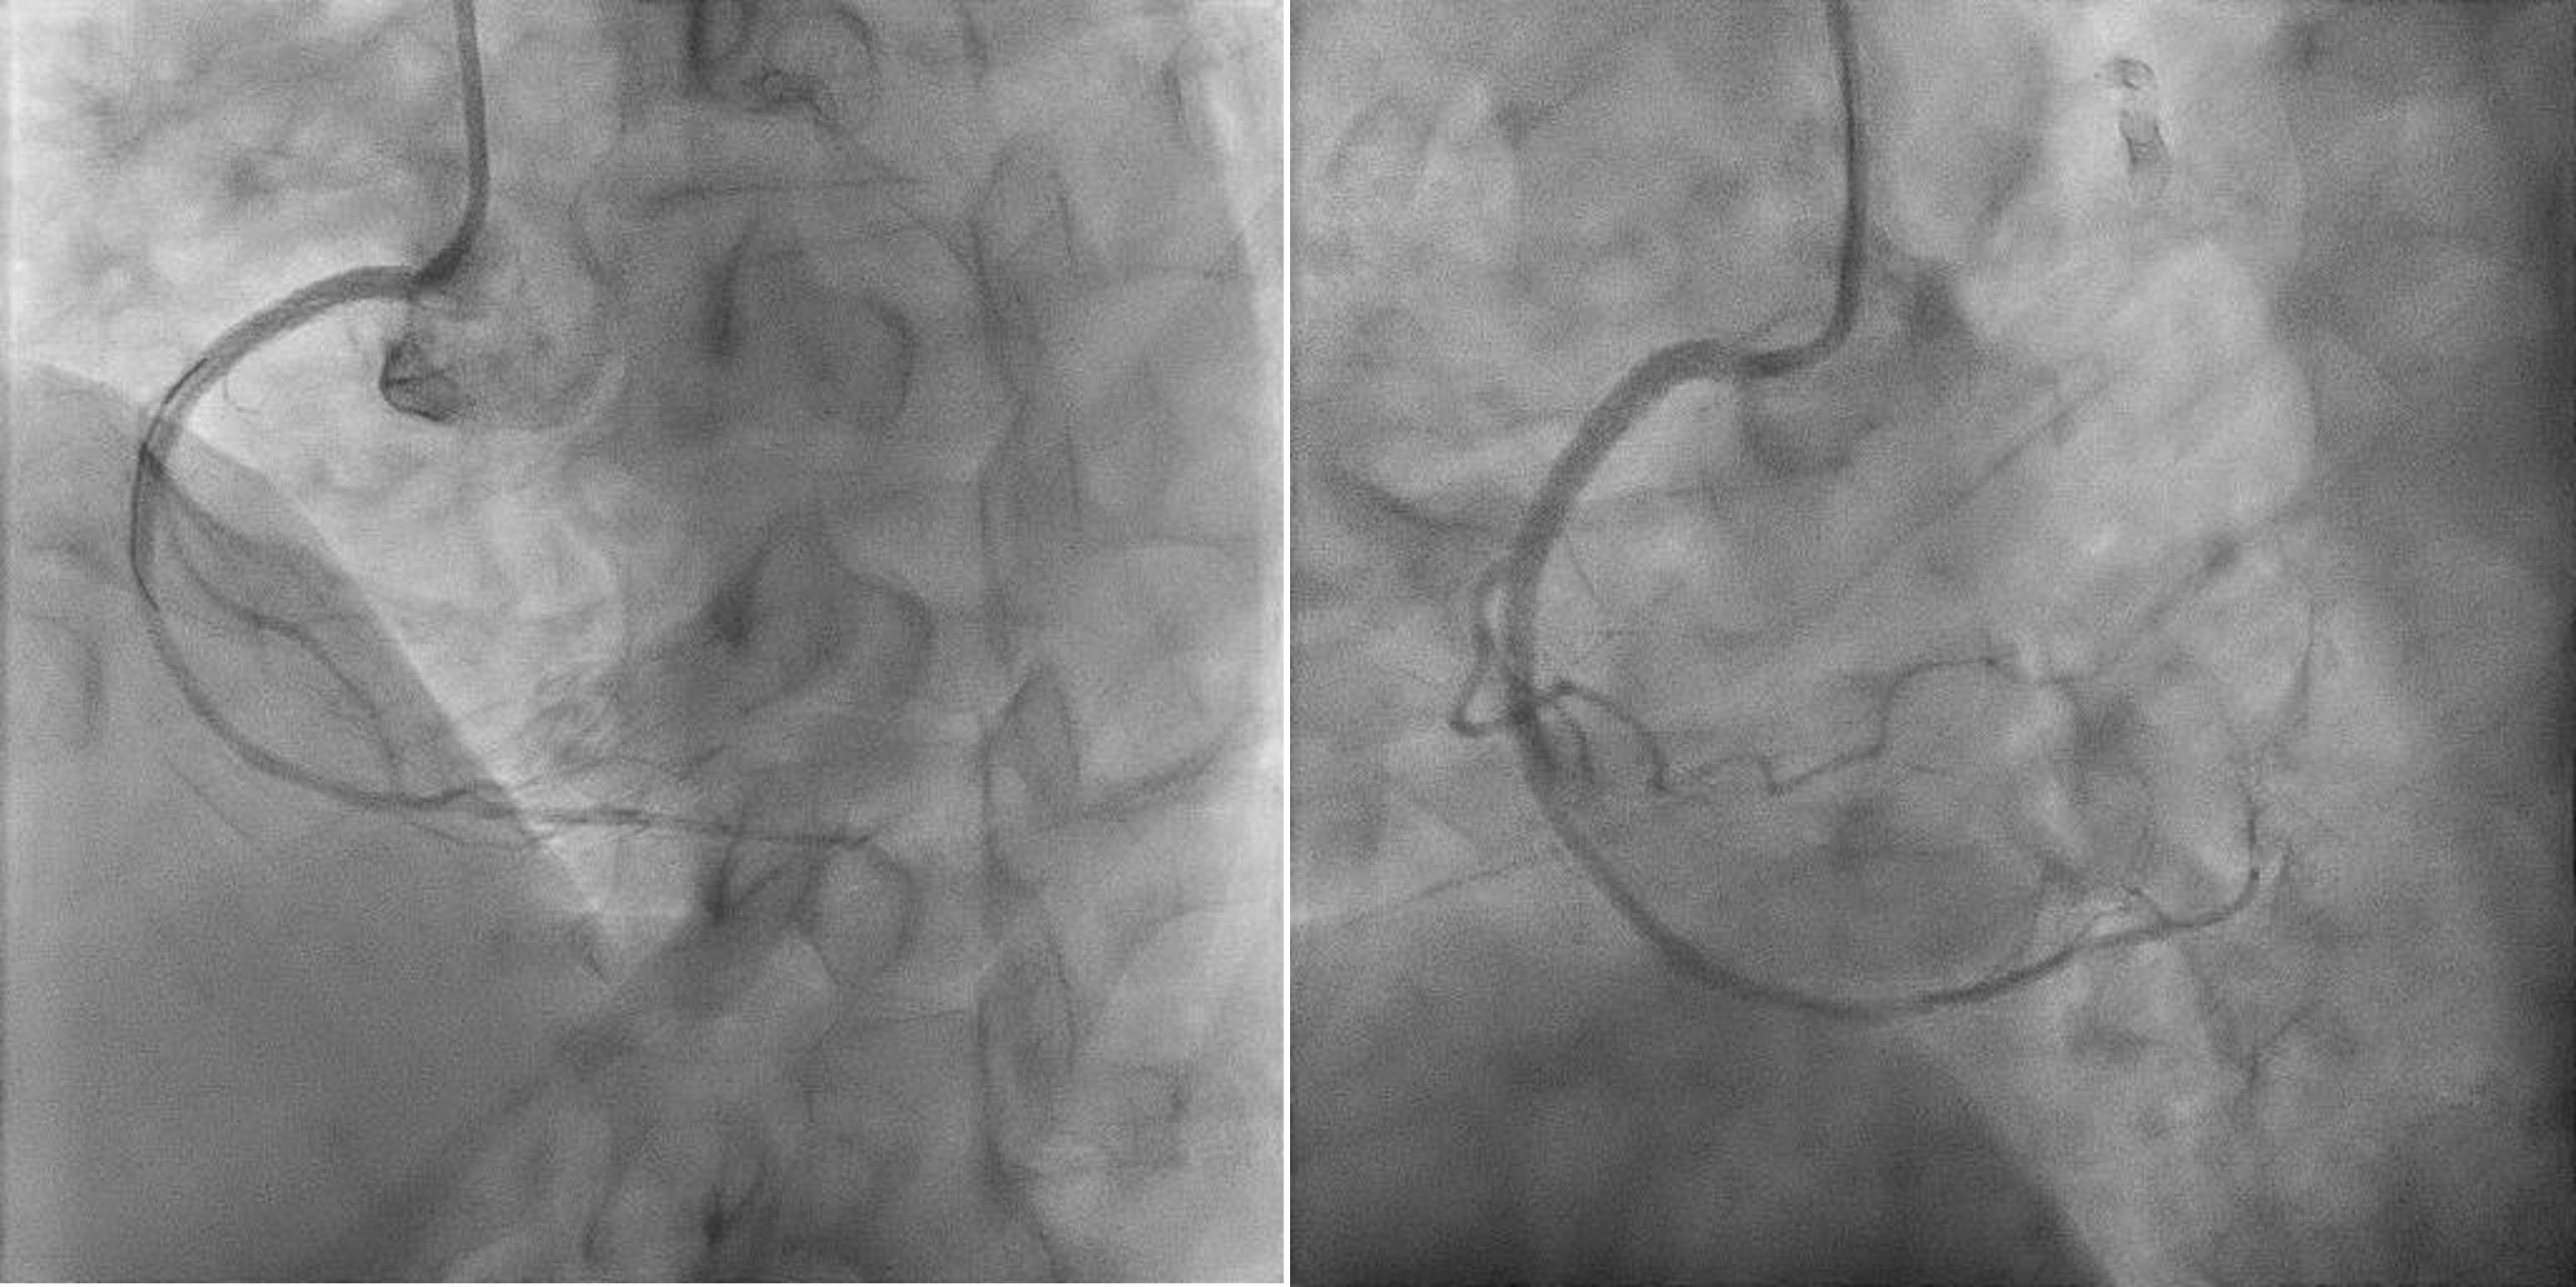

1 Initial predilatation with NC 3.0 > IVUS > Scoring 3.5 up till ostiumIVUS findings showed fibrocalcific+ nodular calcific plaques within and beyond stentRCA sizing was between 3.0mm till 4.0mm proximallyStent was long standing - likely adequately sized Smallest lumen was 1.83mm2 2 Just prior stenting another IVUS performedSmallest lumen (same as previous) improved > 4.0mm23 Long DES 3.0/48mm deployed > Postdilated with NC 3.5 then NC 4.04 Final IVUS performed, stents well opposed, ostium covered adequately but smalles lumen was 4.39mm2

Challenges:1 During PCI, ostium lesion causes BP dampening + ST elevations - catheter kept outside ostium during entire PCI2 Wiring was done from outside - 'air mail'ed into the RCA3 Long stent needed delivering - used 'buddy wire' technique to deliver this4 Findings exact ostium was tough - 'buddy wire' converted to 'sepal wire' for better outcome5 During postdilatation, the 'stubborn' nodule at the distal part of stent, was difficult to prepareEven after stenting, IVUS improvement only. Stent boost was used to delineate the calcific nodular area.

Entire procedure was 36minutes with contrast ~ 150mls. Patient was discharged well with no haemodynamic compromise.

Final RCA Angio.wmv